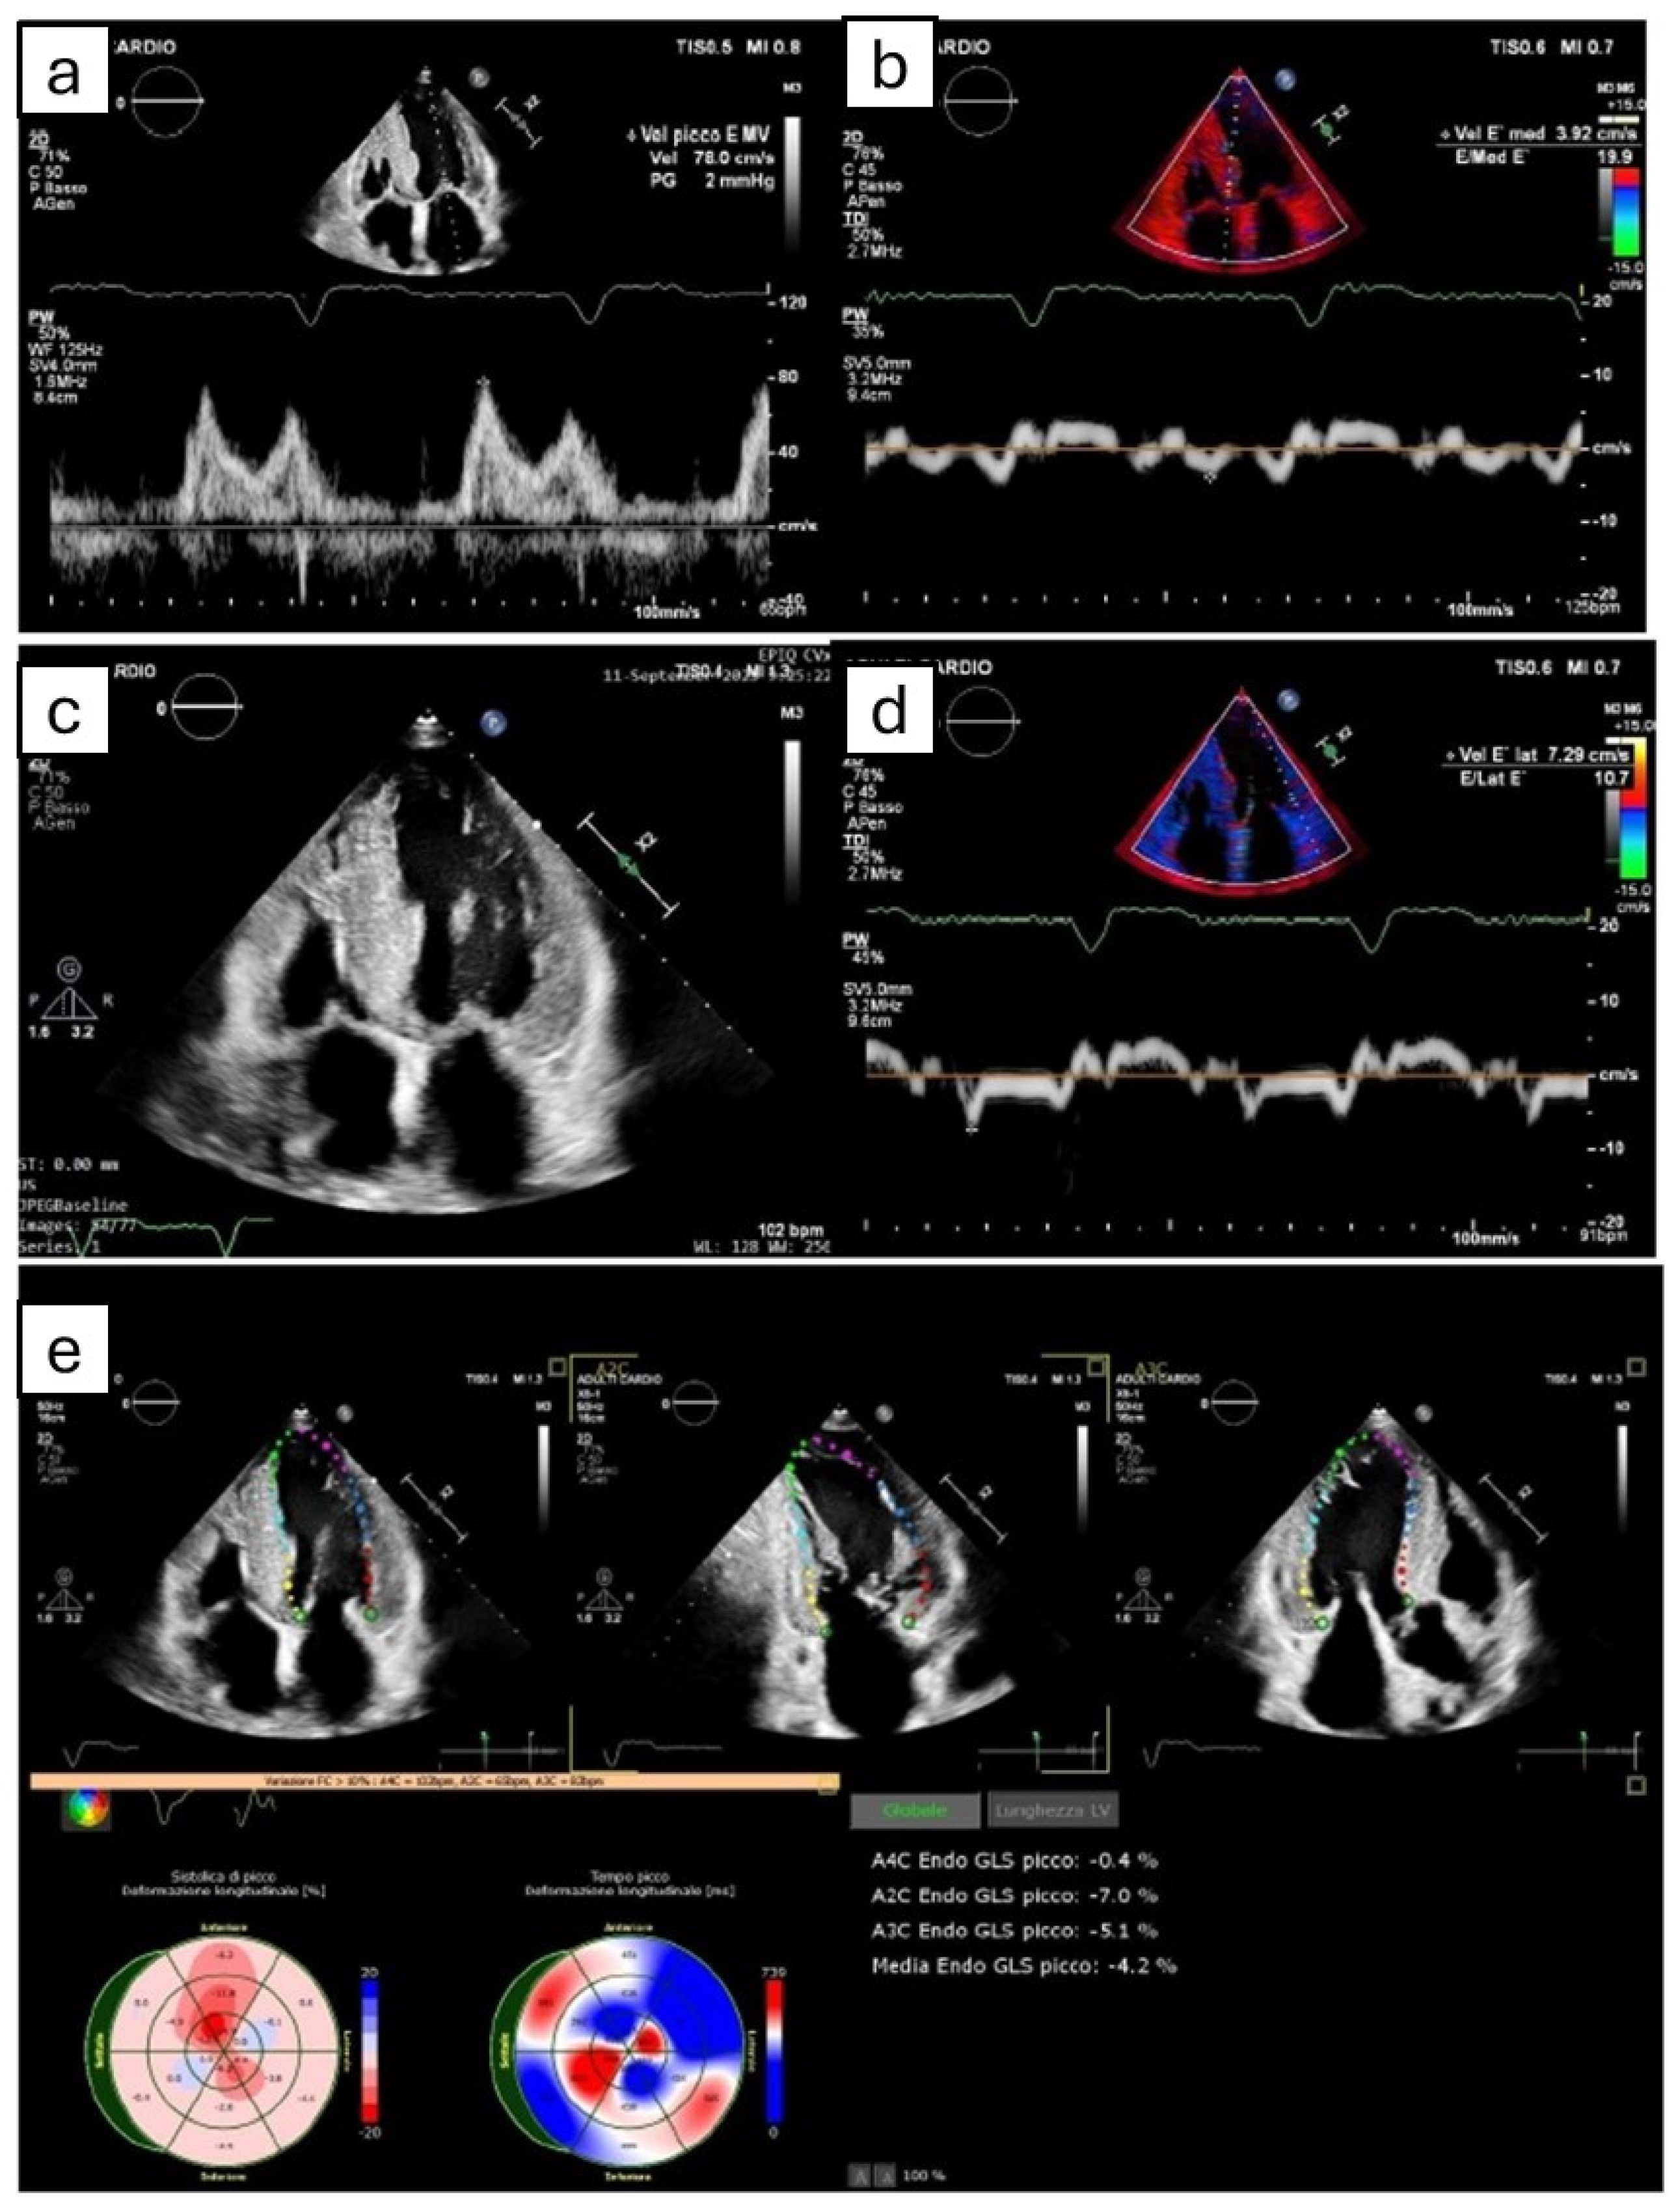

Figure 1.

The figure shows the most common echocardiographic signs that can potentially suggest amyloidotic cardiomyopathy, even though none of them are pathognomonic. (a,b,d) Grade II diastolic dysfunction, with pseudonormal pattern at transmitral power Doppler (a) and reduced septal (b) and lateral (d) e’ velocity at tissue Doppler imaging. (c) Symmetric biventricular hypertrophy, with thickening of interatrial septum. (e) Apical sparing pattern derived by Speckle tracking echocardiography.